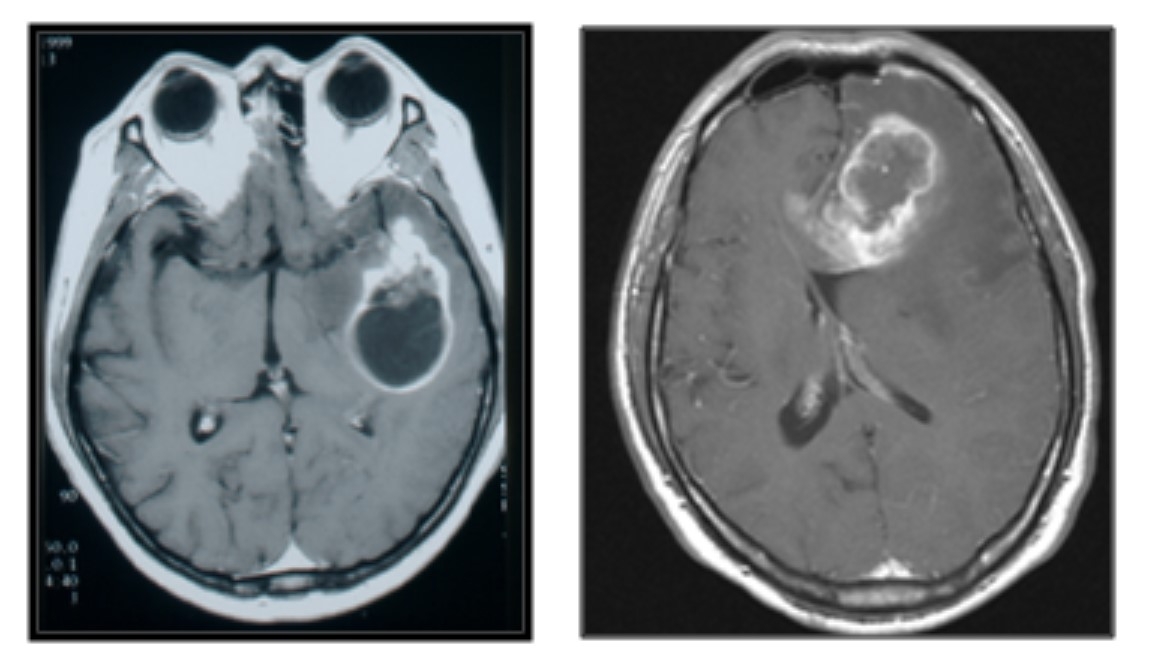

악성 뇌토토사이트 케이 벳(교모세포종) MRI

▶뇌토토사이트 케이 벳 진단은?=뇌토토사이트 케이 벳 진단의 기본은 MRI 검사다. 이는 뇌토토사이트 케이 벳이 의심될 때 뿐만 아니라, 수술 전후 토토사이트 케이 벳의 상태 관찰을 위해 자주 사용된다. 검사에서는 토토사이트 케이 벳 부위를 선명하게 확인할 수 있도록 정맥 조영제를 투여한다.